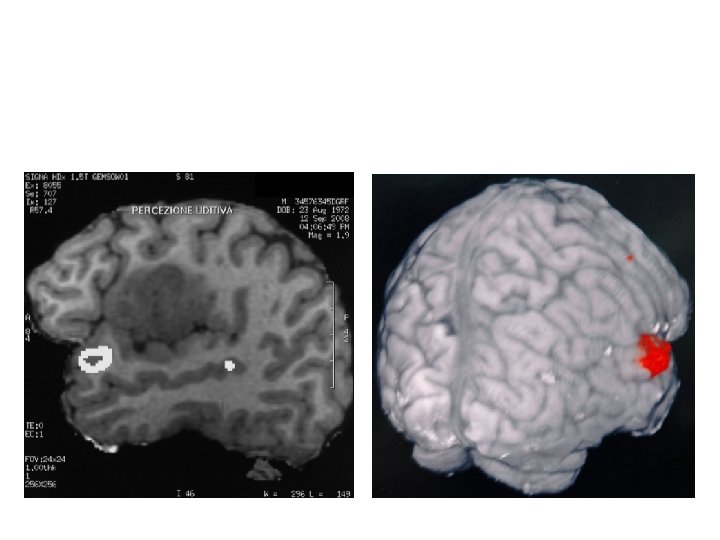

Fuctional MR demonstrating the tumor boundaries and the Uditive area without pallido-capsular involvement

Functional MR demonstating temporal opercular region tumor involvement and uditive area to avoid during the tumor approach (no distraction of the opercula)